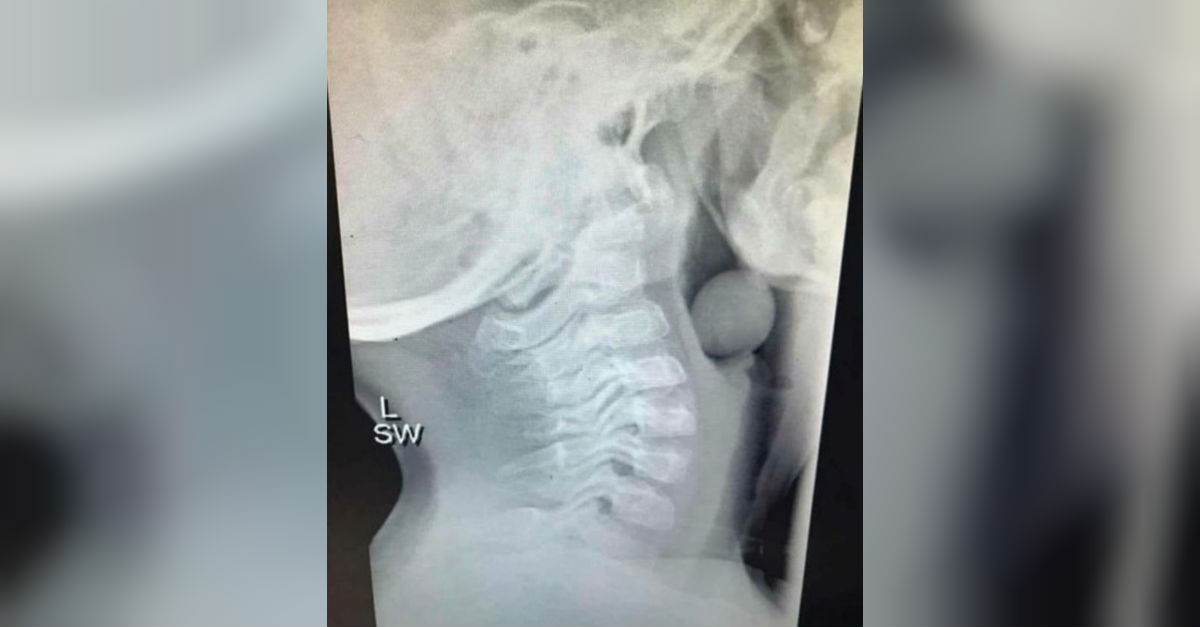

XRay Reveals Grape Stuck In Child's Throat

From www.jumblejoy.com

XRay Of A Grape In Child’s Throat Is Going Viral JumbleJoy Green Grapes In The Throat Meaning the spiritual meaning of grapes goes beyond their role as a simple fruit, evoking a sense of abundance,. The color of phlegm may help indicate the cause of a cough and excess. it causes an allergic reaction usually limited to your lips, mouth and throat. color of phlegm and what it means. This rich symbolism can be. Green Grapes In The Throat Meaning.

XRay Reveals Grape Stuck In Child's Throat Green Grapes In The Throat Meaning this article explores the multifaceted meanings associated with grapes, shedding light on their historical. “the parents have eaten sour grapes, and the children’s teeth are set on edge.” we may never have eaten a sour. the spiritual meaning of grapes goes beyond their role as a simple fruit, evoking a sense of abundance,. This rich symbolism can. Green Grapes In The Throat Meaning.

From www.elitereaders.com

Blogger Shares Xray Of A Grape Stuck In Boy's Throat To Warn Against Green Grapes In The Throat Meaning “the parents have eaten sour grapes, and the children’s teeth are set on edge.” we may never have eaten a sour. the spiritual meaning of grapes goes beyond their role as a simple fruit, evoking a sense of abundance,. This rich symbolism can be seen. color of phlegm and what it means. this article explores the. Green Grapes In The Throat Meaning.